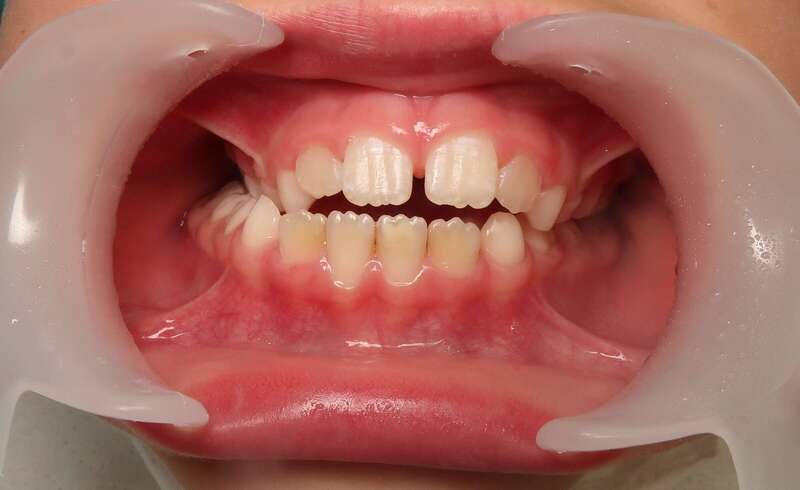

Cas n°3 traité par aligneurs (interception) - enfant

Intervenir dès 8 ans avec cette approche offre des bénéfices structurels :

• Symétrie Faciale : En éliminant le glissement de la mâchoire, on assure que le visage se développe de manière droite et harmonieuse.

• Confort Articulaire : Le recentrage prévient les tensions et les pathologies futures des articulations de la mâchoire (douleurs, craquements).

• Expérience Positive : L'absence de douleur et la simplicité des aligneurs favorisent une excellente acceptation du traitement par l'enfant.

• Simplification du futur : "Remettre la croissance sur les rails" permet souvent d'éviter des traitements beaucoup plus complexes (voire chirurgicaux) à l'adolescence.